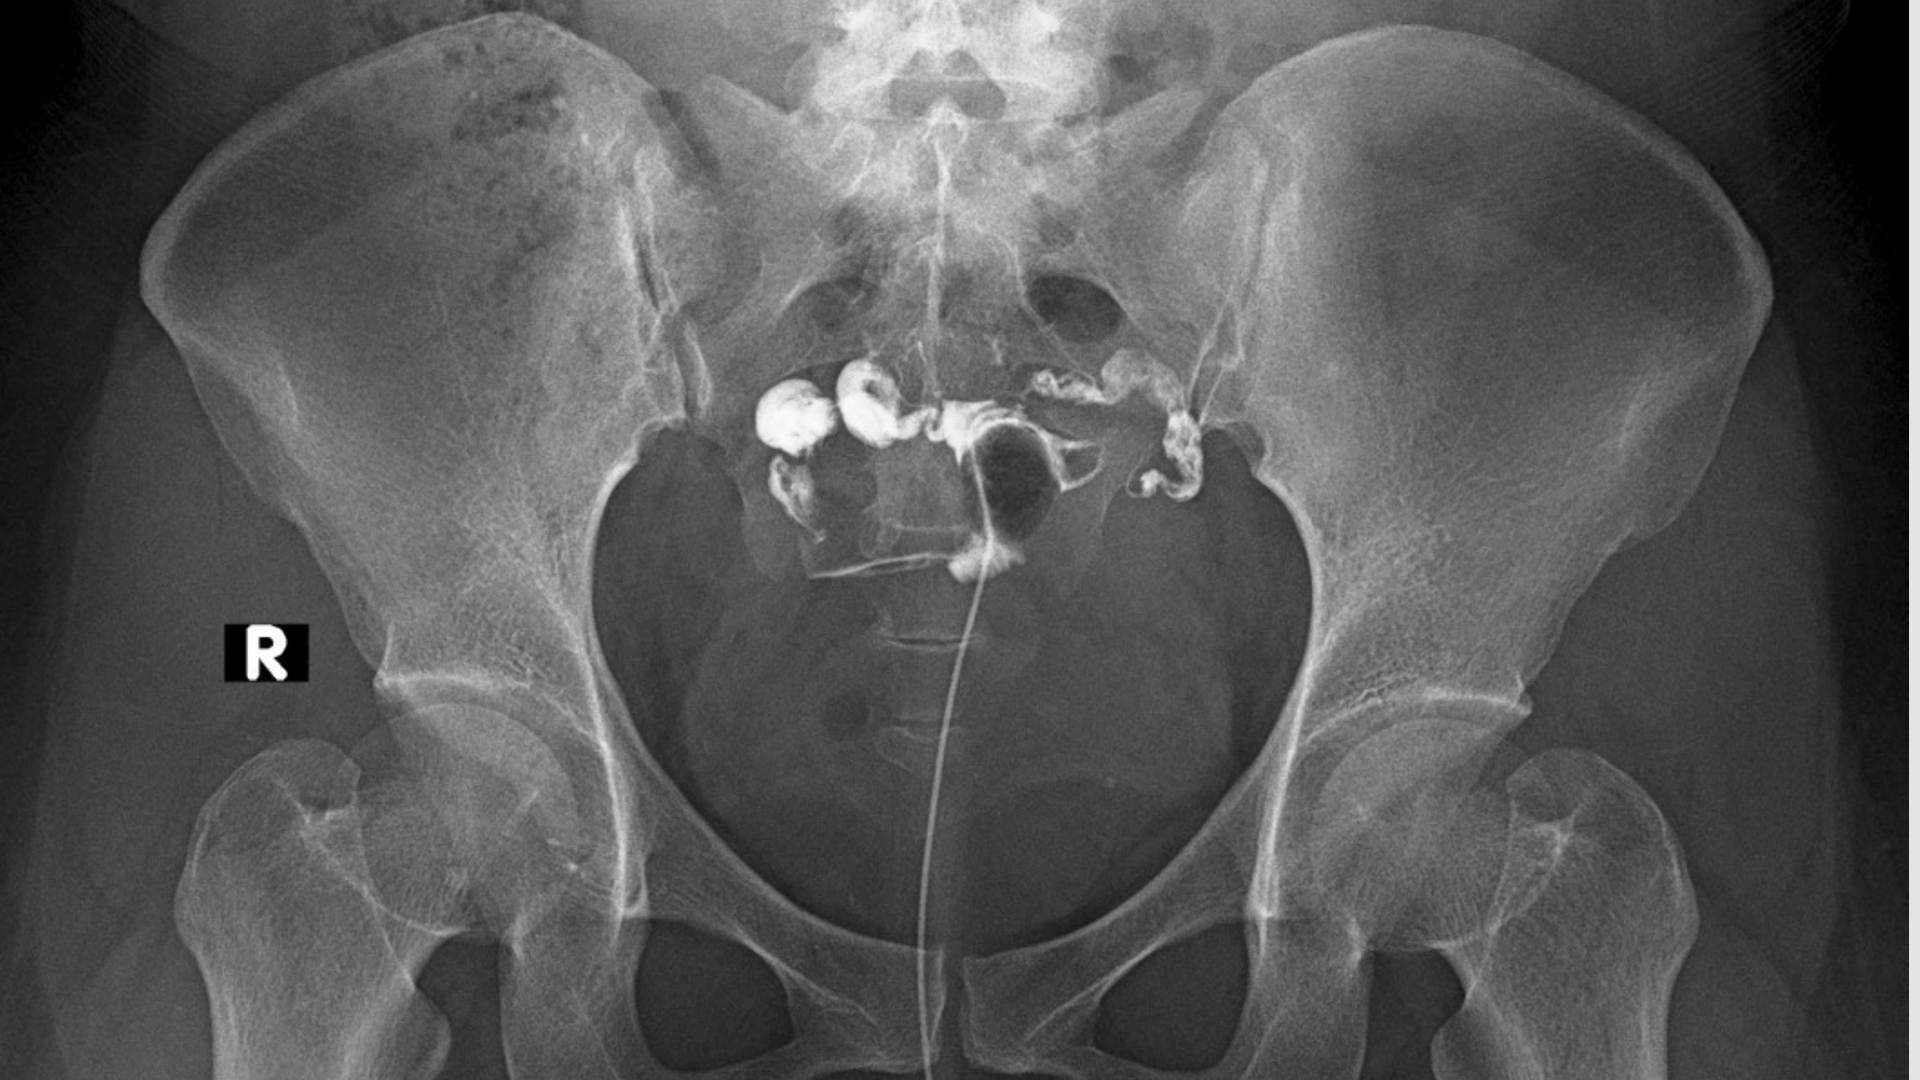

Hystéro-Salpingographie

L’hystéro-salpingographie est un examen radiologique qui permet d’étudier l’utérus et les trompes de Fallope.